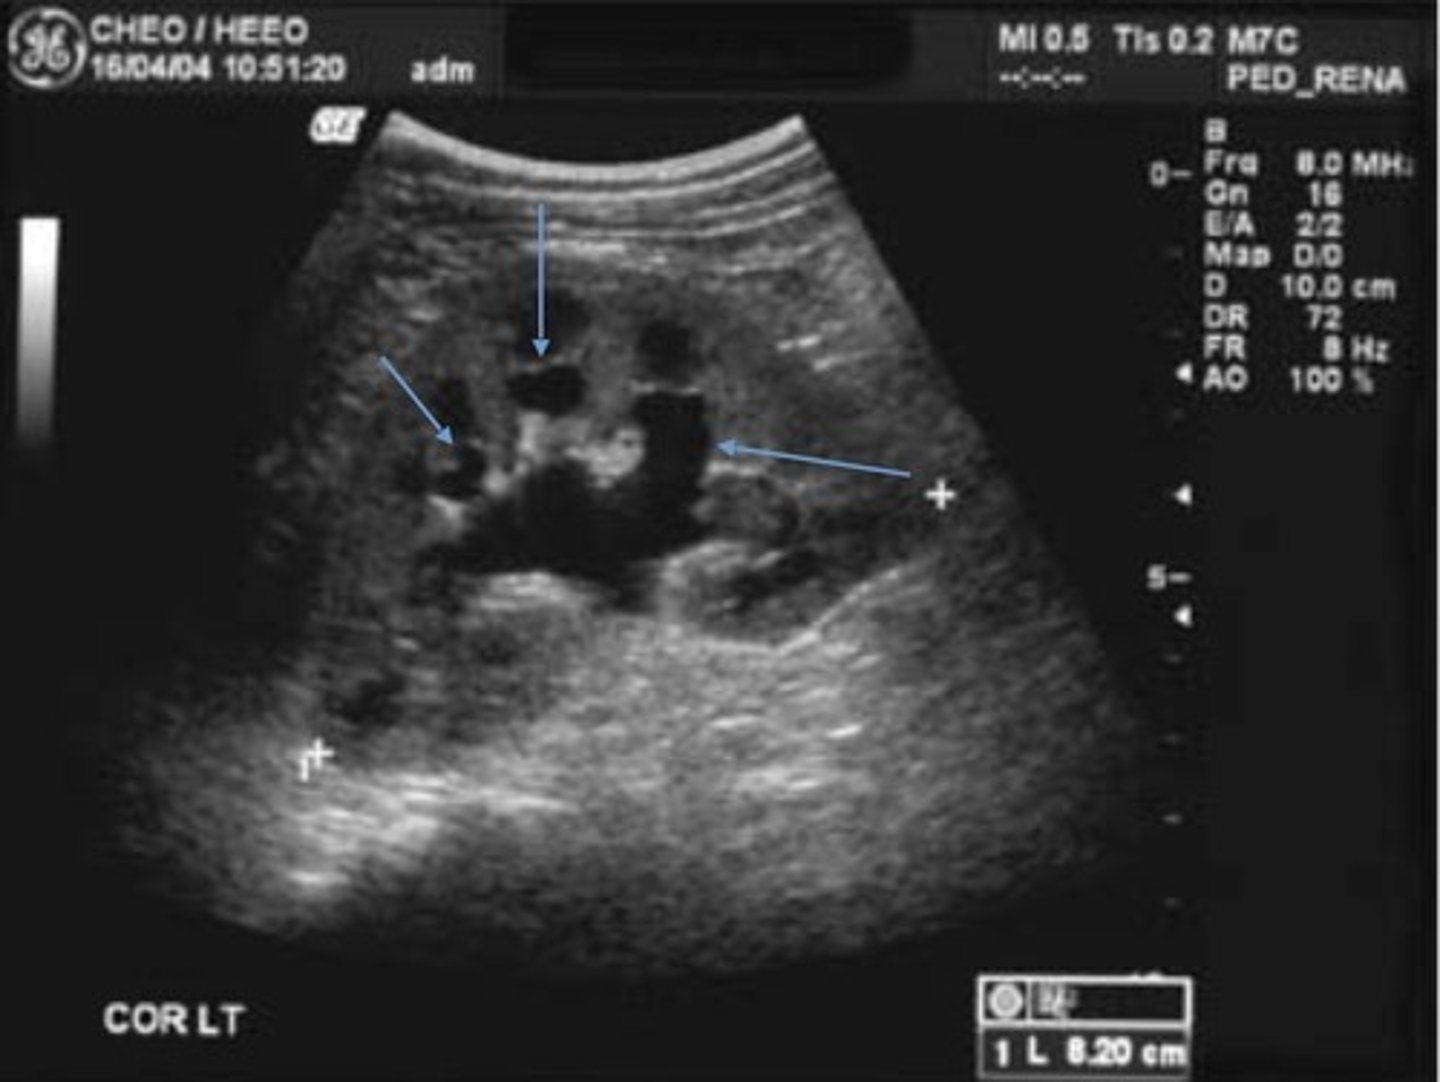

Grade 3 Hydronephrosis

Pelvis is > 10 mm

Marked dilation of calyces

Cortex is normal